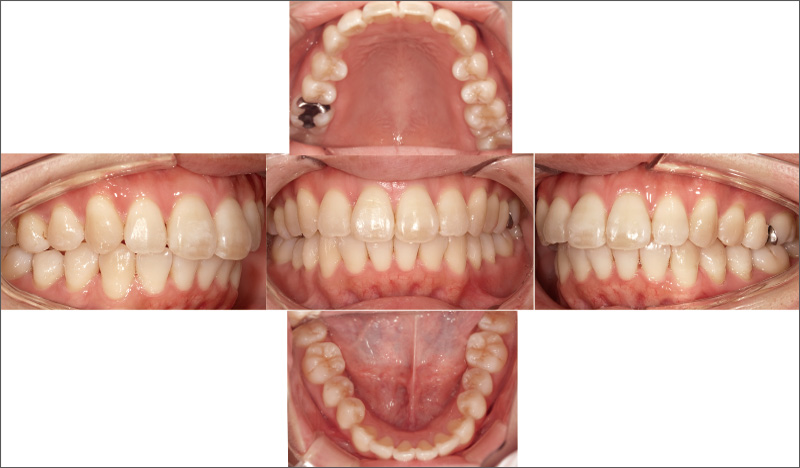

症例2-2 20週という短期間で歯列不正を改善。「クリンチェック治療計画」を再現性高く実行できた。「iGo」は矯正の範囲などに制約はあるが、歯牙移動について非常に再現性が高いことがわかる。 -

症例2-1 ₂の形態異常を主訴に来院した30代女性。審美回復には矯正治療が必要と説明したが、全顎的な矯正は希望されなかった。半年以内に終了する「iGo」による部分矯正治療には同意が得られたため、₁抜歯後に治療を開始した。 -